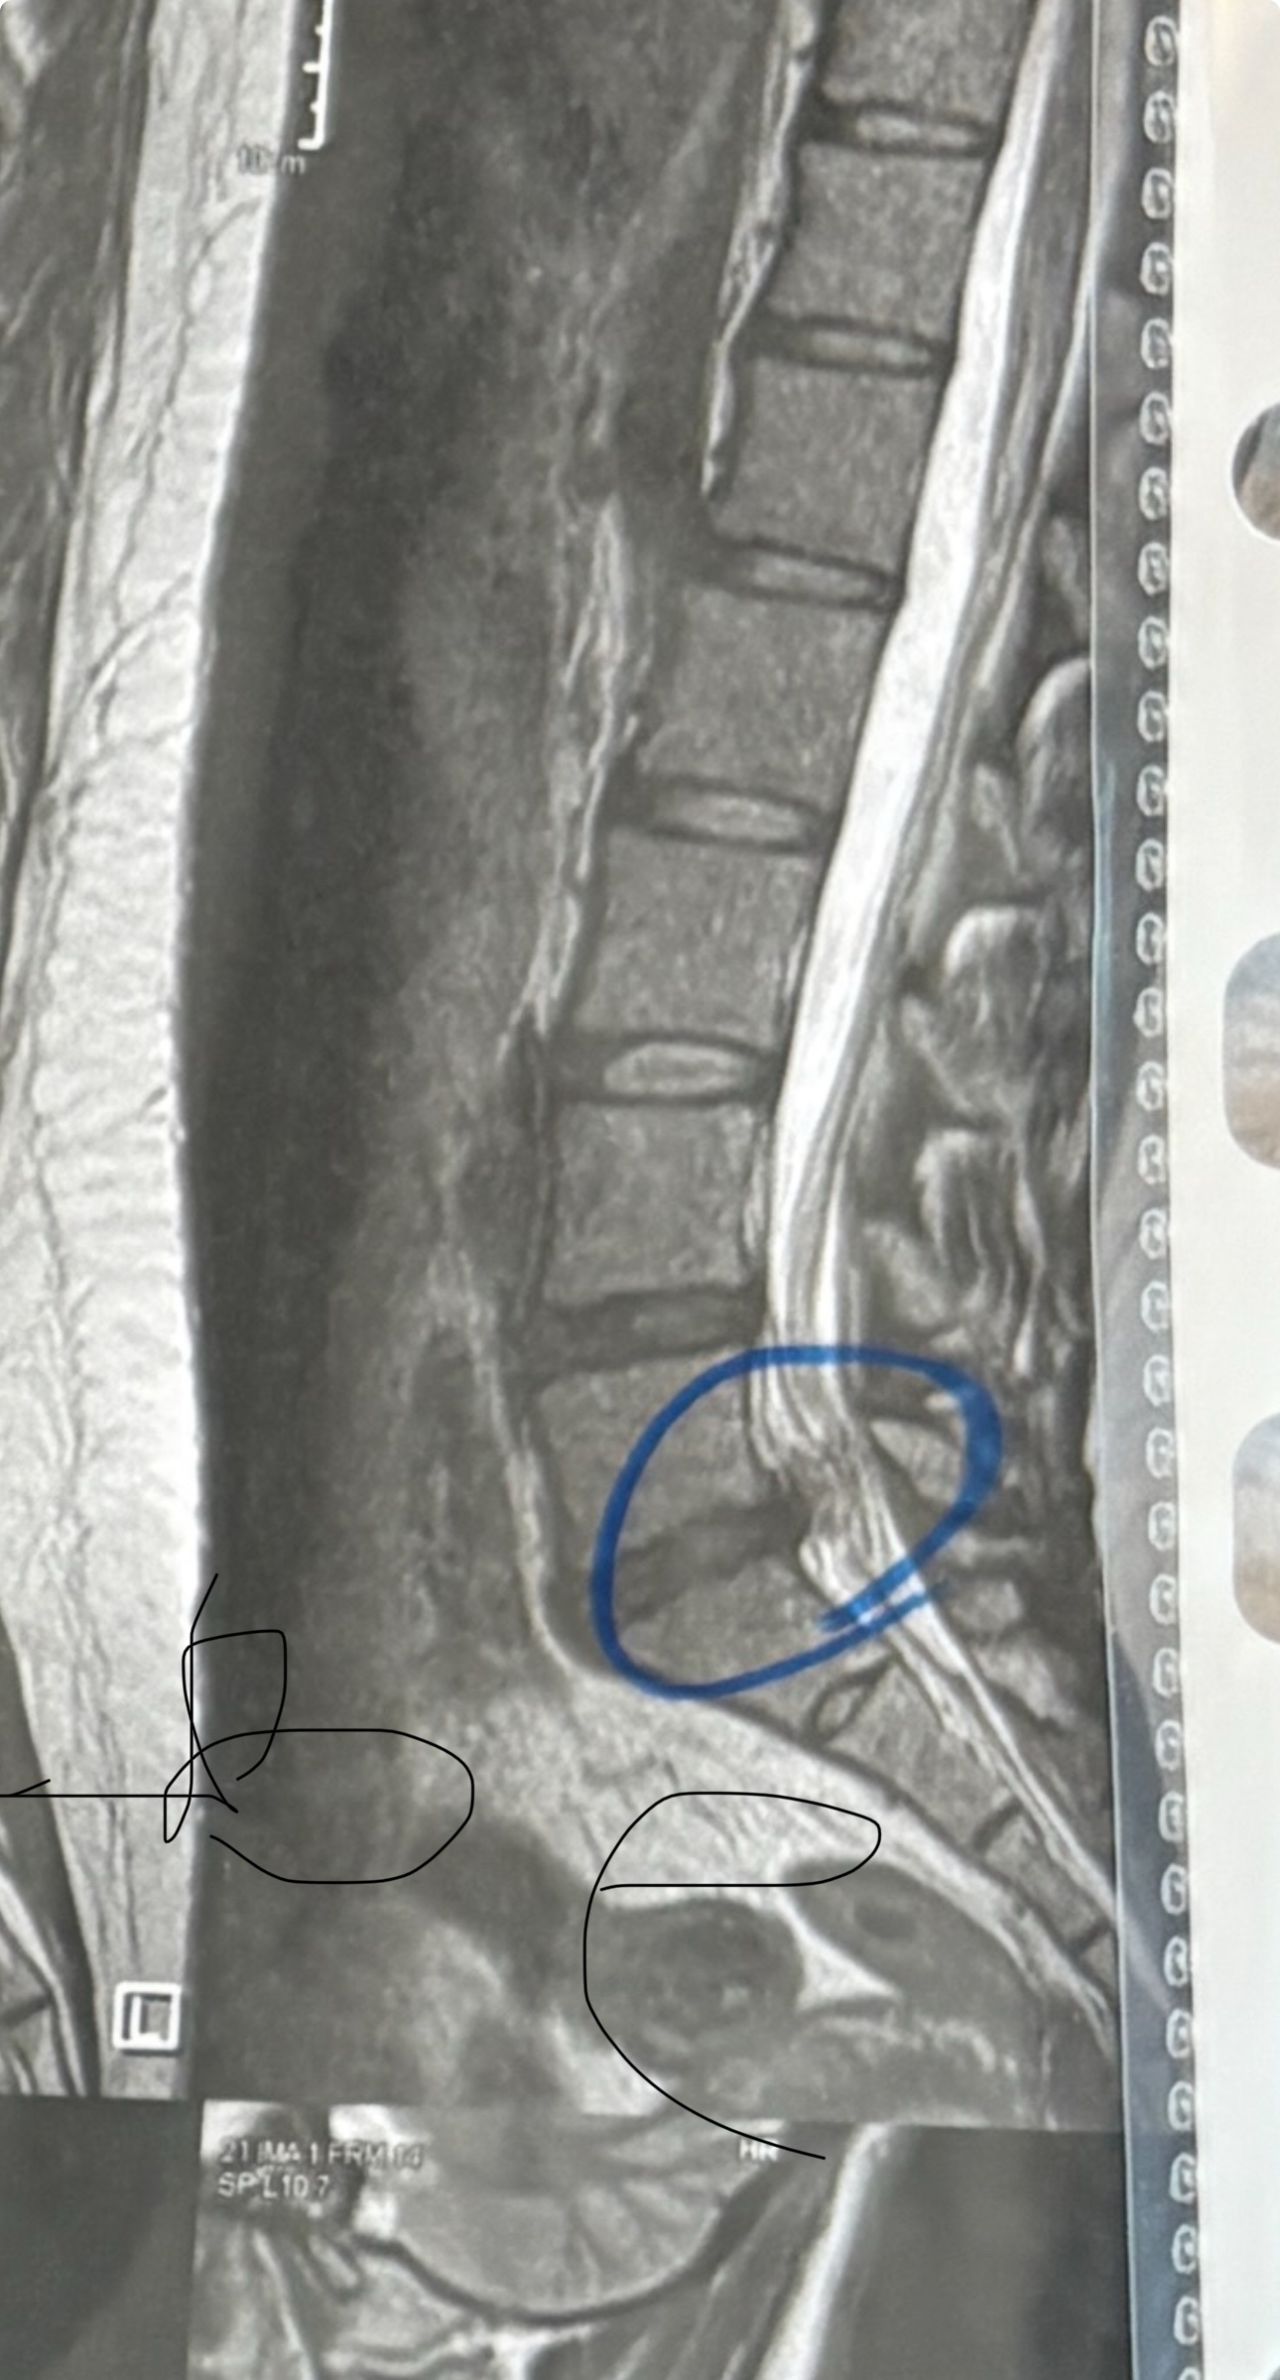

41 years old man presented to my clinic in October 2023 with acute and sever R neck pain with radicular pain to his R upper extremity along C6 dematom since 2 weeks ago. Examination didn’t show any upper motor signs. Was suggested urgent surgery

I ordered EMG/ NCV : showed mild R C6, C7 irritation without any active axonal loss

In his MRI was reported R. para R. IVF Massive extrusion. I decided to control his pain and manage this patient with reevaluation of patient every other session. For 5 sessions i just used acupuncture and laser and IFC and mild adjustments to his R. T3-T7 and mild arthosteem to above and below involved segment. Cervical adjustment considered contraindicated for this patient. From session 6th- 8th i started to use mild/gentle cervical decompression. He used soft cervical collar all the time. His pain decreased by 80 percent

I gave him cervical traction pump to be used 3-5 times per day at home for the next 3 months and i released the patient. He was evaluated every week once for one month and after that every 2 weeks. After 3 month I repeated MRI. Size of the herniated disc was reduced greater than 50 percent. Asked him to do another mri in 6 months

In general: Precise selection of the patients, examination,diagnosis, plan of management, reevaluation and treatment can be done by doctors of chiropractic for the patients with spinal disc herniation and stenosis Moreover giving reasonable time to these kind of patients under direct supervision by their chiropractic doctors can prevent unnecessary surgery. Proper selection of these kind of patients is another important fact that can be done precisely by chiropractors.

MRIs before and after proper management of this patient: